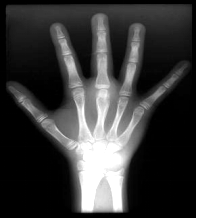

图2-4幼年特发性关节炎活动期

4岁,双手多个指间关节周围软组织肿胀

关节间隙模糊、变窄,右腕骨化中心提

前出现及桡骨过长(骨生长加速所致)